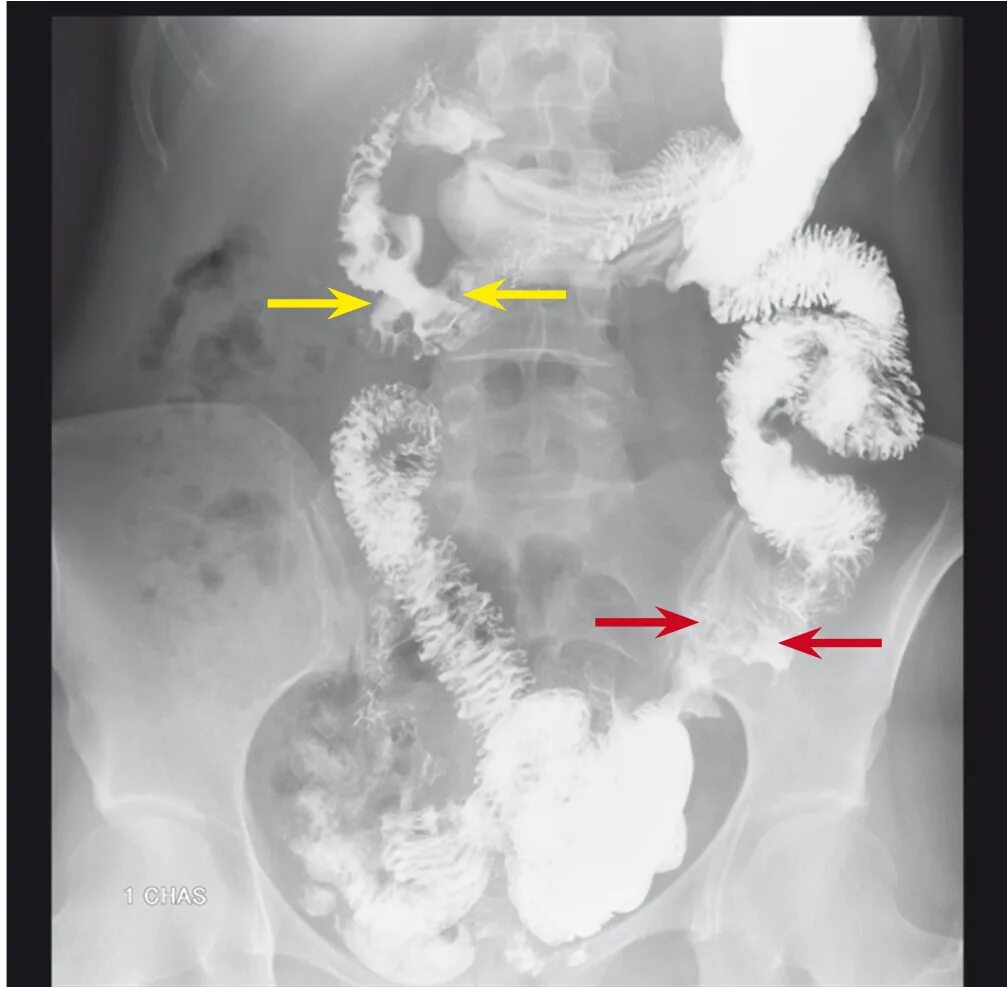

Метастазы при раке сигмовидной кишки